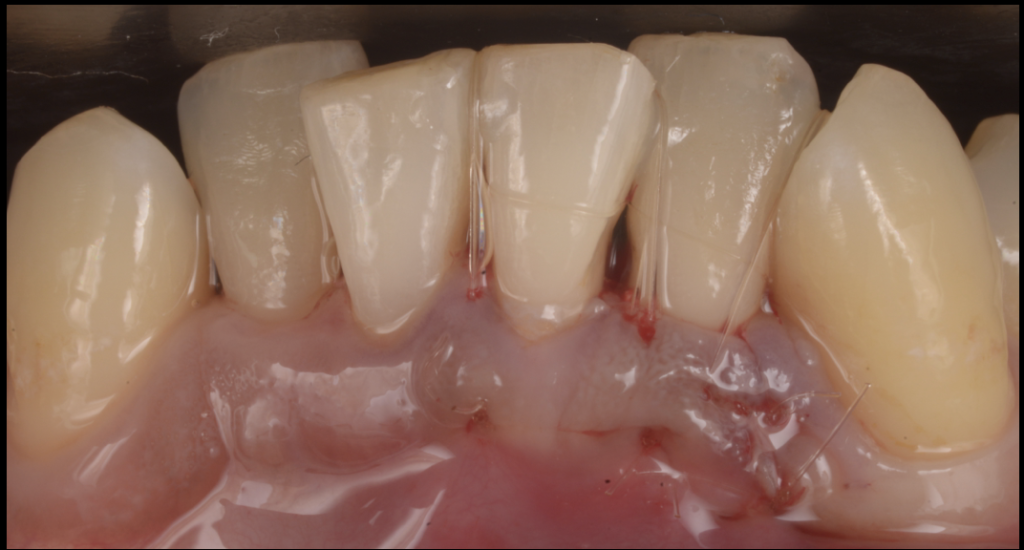

③ 歯ぐきをやさしく縫合

最後に、歯ぐきを元の位置へ戻し、

できるだけ血行を妨げないように細い糸で縫合します。

縫い方ひとつで、術後の腫れや痛み、治癒のスピードが変わってきます。